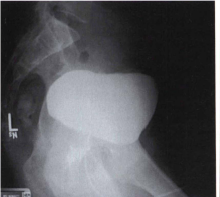

c. Hasil gambaran menunjukan bahan kontras mengisi Vesica Urinaria, rectum dan colon desenden, hal ini menunjukan pasien mengalami kelainan adanya Fistula yang menghubungkan Vesica Urinaria dengan rectum.